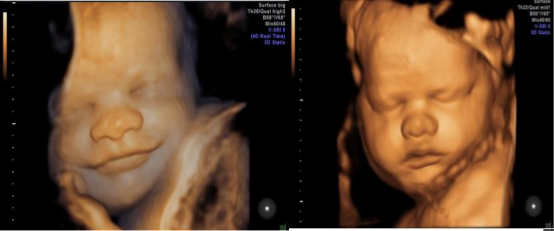

新一代E10拥有完美的图像质量、高端的成像技术及极快速的处理能力,在缩短患者检查时间的同时,更清晰的显示超声所见,让患者更早时间跟自己的宝宝见个面。

新一代E10在提高图像质量及四维图像处理的同时,也提高了胎儿先天性畸形的检出率,在一定程度上避免了致死性畸形胎儿的娩出,提高各位患者的选择性和生活质量。

中孕期彩超胎儿颜面部及脊柱成像,把胎儿看的真真切切,明明白白,让您提前观察到宝宝的一举一动,一颦一笑,准妈妈们可以亲眼目睹胎儿在子宫内的相貌和动作,在感叹生命发生的同时,留下一段珍贵的影像,一段属于您和宝宝最早最珍贵的回忆。

故三维、四维容积超声对诊断胎儿神经系统学,表面成像的胎儿畸形的筛查有更直观的感受,更明确的帮助诊断。